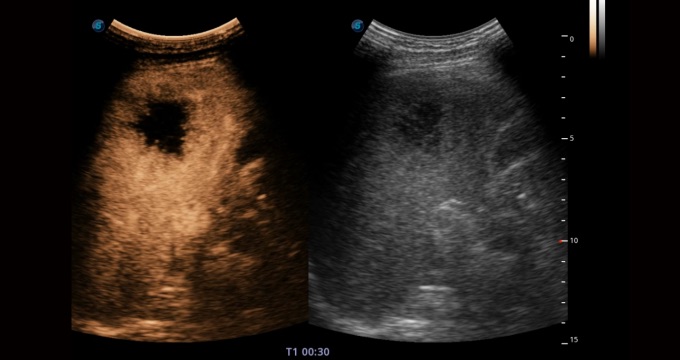

造影成像功能和定量分析工具包使醫(yī)生能夠準(zhǔn)確的評(píng)估血流灌注情況。獨(dú)特的動(dòng)態(tài)聲壓控技術(shù)有效控制造影劑的聲壓,保證造影劑持續(xù)時(shí)間,方便醫(yī)生觀察病變灌注的延遲相位。

腹部應(yīng)用